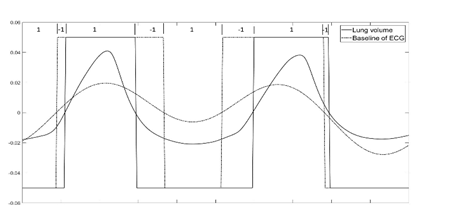

A match in signal phase occurs when the “Sign match index” is positive at that time (i.e., the reference signal and the test signal have the same sign). A negative match index would then represent a phase mismatch between the reference and test signals. Figure 7 shows an example of testing phase match between lung volume change (reference signal) and ECG baseline wonder (test signal) over a period of 10 seconds

Figure 7 Traces of reference signal (Lung volume change) and test signal (baseline wondering of ECG) plotted along with their sign. The sign of each signal is also plotted, and the Sign match index is shown on the top of the graph. A Sign match index > 0 shows the region of phase match between the signals while a negative value indicates phase mismatch.